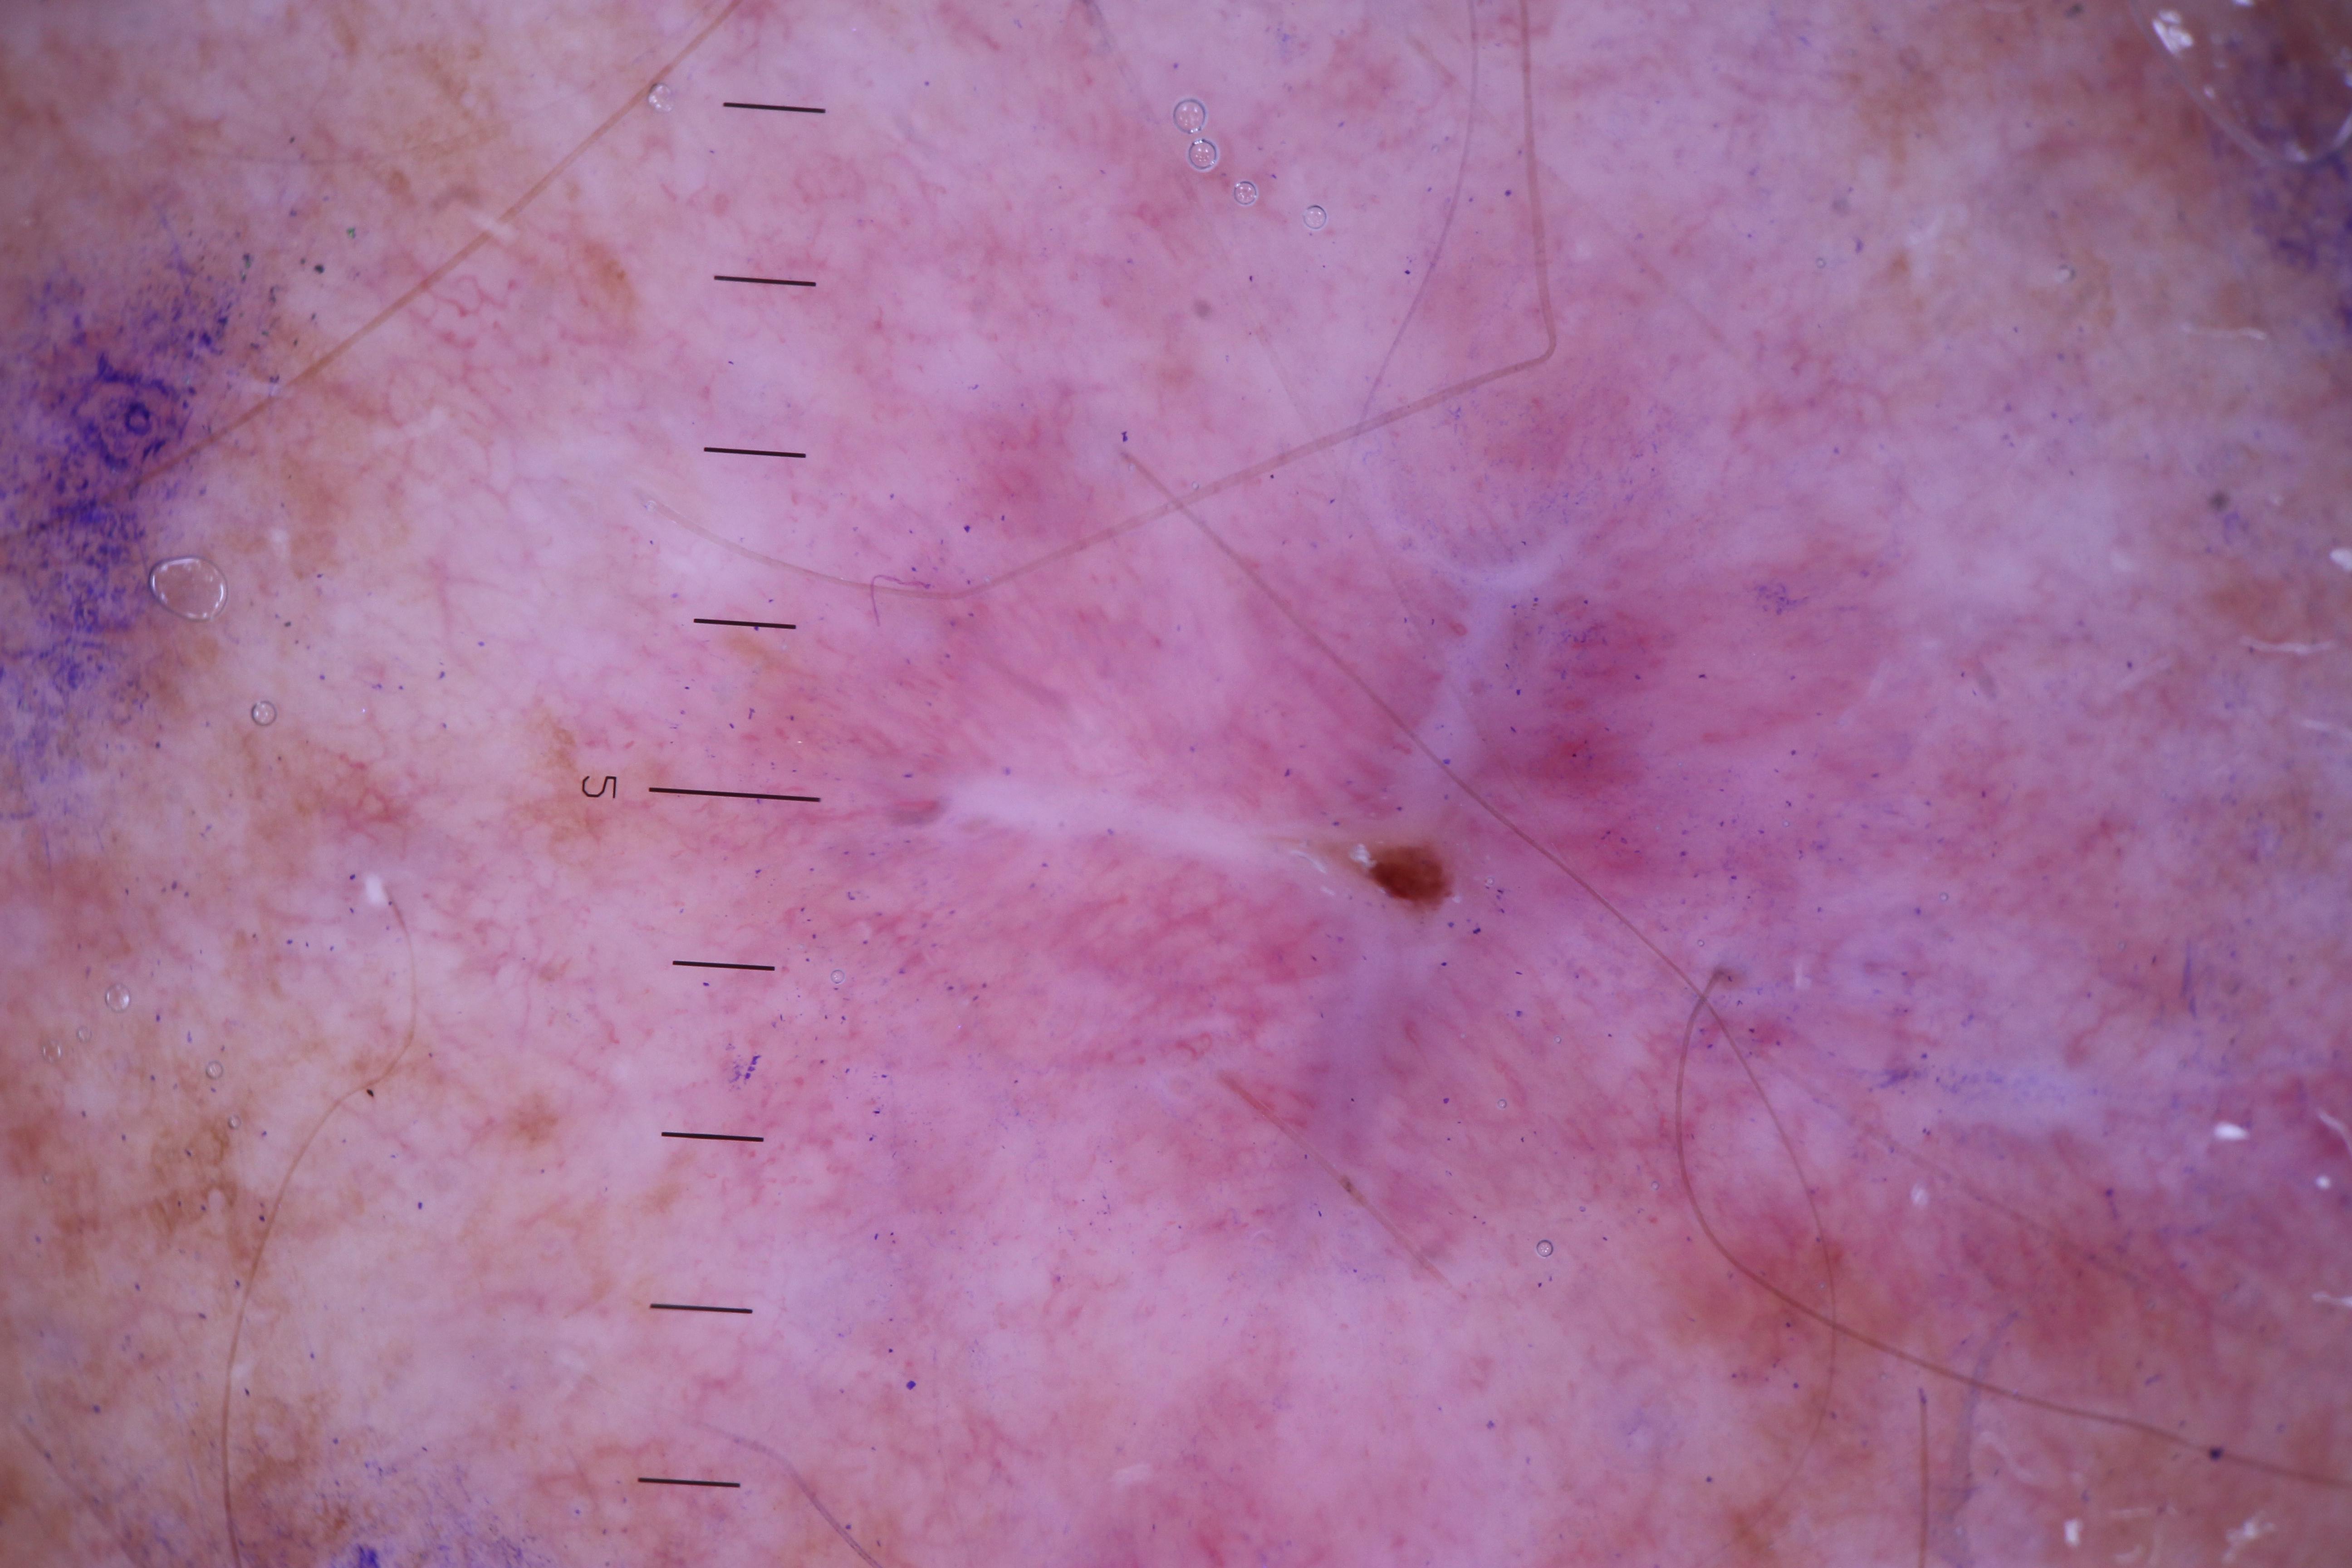

{

"acquisition_day": 106,

"age_approx": 50,

"anatom_site_general": "posterior torso",

"concomitant_biopsy": false,

"diagnosis_1": "Benign",

"diagnosis_confirm_type": "serial imaging showing no change",

"fitzpatrick_skin_type": "II",

"image_type": "dermoscopic",

"lesion_id": "IL_5811983",

"patient_id": "IP_2105363",

"sex": "male"

}